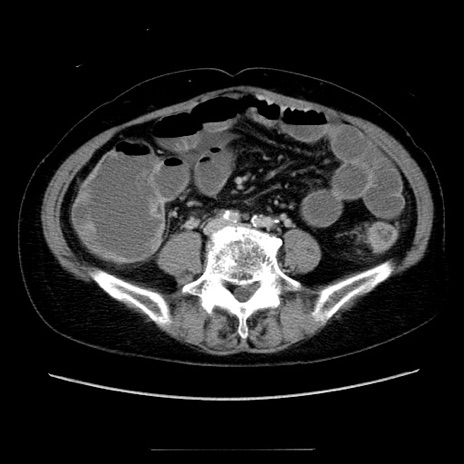

症例5(横断像)

【症例】70歳代女性

【主訴】お腹が張る

【現病歴】1週間くらい前から腹部膨満の自覚あり。昨日夜から増悪したため、本日救急外来受診。

【身体所見】意識清明、BT 36.5℃、BP 165/106mmHg、HR 80bpm、SpO2 98%、腹部:膨満、軟、自発痛・圧痛なし、触診にて不快感あり、腸蠕動音:減弱

【データ】WBC 12600、CRP 1.04